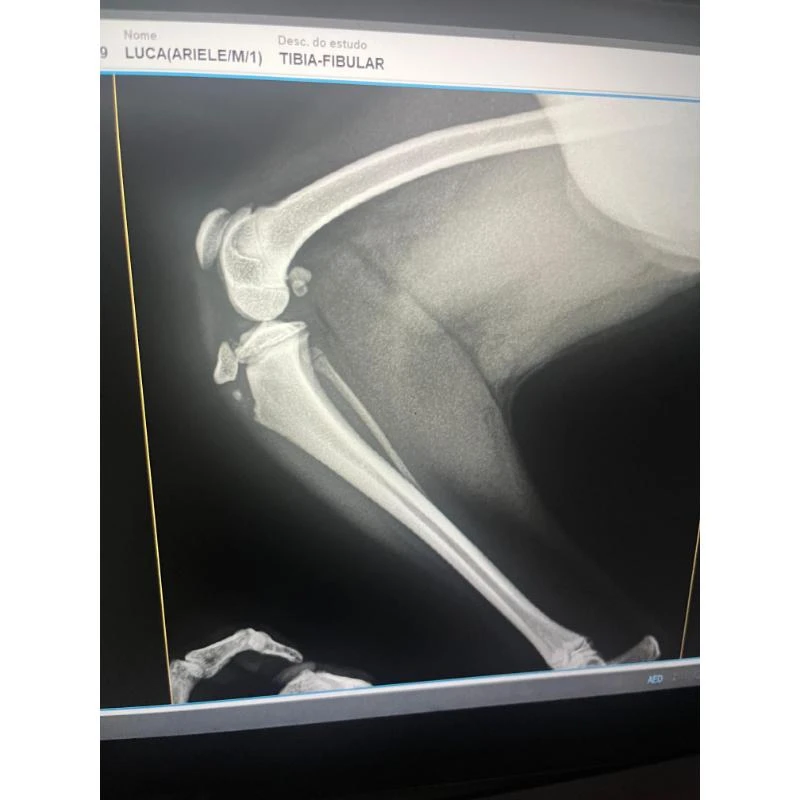

Com atendimento 24 horas, a clínica oferece uma ampla gama de serviços, incluindo hemodiálise, internação assistida, clínica geral, cardiologia, oftalmologia, ortopedia, oncologia, neurologia, entre outros.